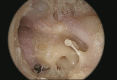

An overview of endoscopic ear surgery in 2018

Objective: To provide an overview of Endoscopic Ear Surgery, its development, principles, and penetration in otology practice in 2018.

Results: The number of publications on use of endoscope has increased from 6 in 1990 to an accumulated total of 451 in 2018. There has been a clear shift in the area of interest away from diagnostic endoscopy, to endoscope-assisted surgery, and lately, to transcanal endoscopic ear surgery (TEES). Survey results further documented the increased awareness of the value of the endoscope and its increased use in clinical practice.

Conclusion: TEES has gained traction as a subject of research interest and in clinical practice and has lately dominated the discussion on the use of endoscope in otology.